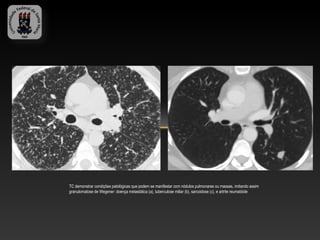

TC demonstrar condições patológicas que podem se manifestar com nódulos pulmonares ou massas, imitando assim

granulomatose de Wegener: doença metastática (a), tuberculose miliar (b), sarcoidose (c), e artrite reumatóide